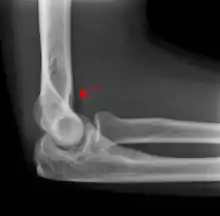

Fat pad sign

The fat pad sign, also known as the sail sign, is a potential finding on elbow radiography which suggests a fracture of one or more bones at the elbow. It is may indicate an occult fracture that is not directly visible. Its name derives from the fact that it has the shape of a spinnaker (sail).[1] It is caused by displacement of the fat pad around the elbow joint. Both anterior and posterior fat pad signs exist, and both can be found on the same X-ray.

The fat pad sign is invaluable in assessing for the presence of an intra-articular fracture of the elbow. An anterior fat pad is often normal. However a posterior fat pad seen on a lateral x-ray of the elbow is always abnormal. The patient will be unable to flex their elbow and requires orthopaedic input.[2]